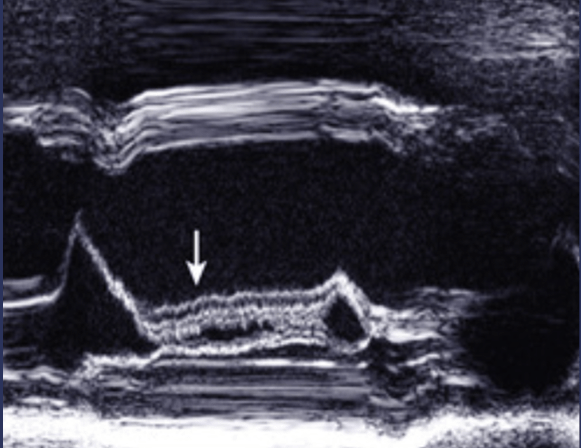

The name for this indirect sign of aortic valve regurgitation on M-mode.

What is anterior mitral valve leaflet diastolic fluttering?